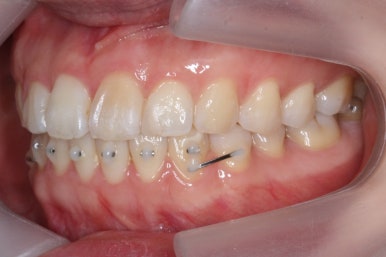

그리하여 부산앞니교정 키다리아저씨치과에서 장치를 재부착하고 일종의 재교정을 들어갔습니다.

유지장치를 하지 않은 상태였기 때문에 원래대로 앞니가 되돌아간 것을 볼 수 있습니다.

이번에는 약간 다른 양상으로 조절을 하기 위해서 MTA 장치 말고 일반 브라켓을 붙이기로 하였습니다.

이번에 사용한 장치는 클리피씨라고 하는 세라믹 자가결찰 장치였습니다.